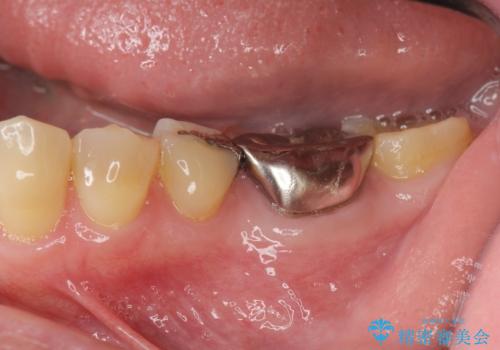

噛むと痛い銀歯 根管治療を伴うやりかえ

奥歯の被せ物のやり直し 精密根管治療